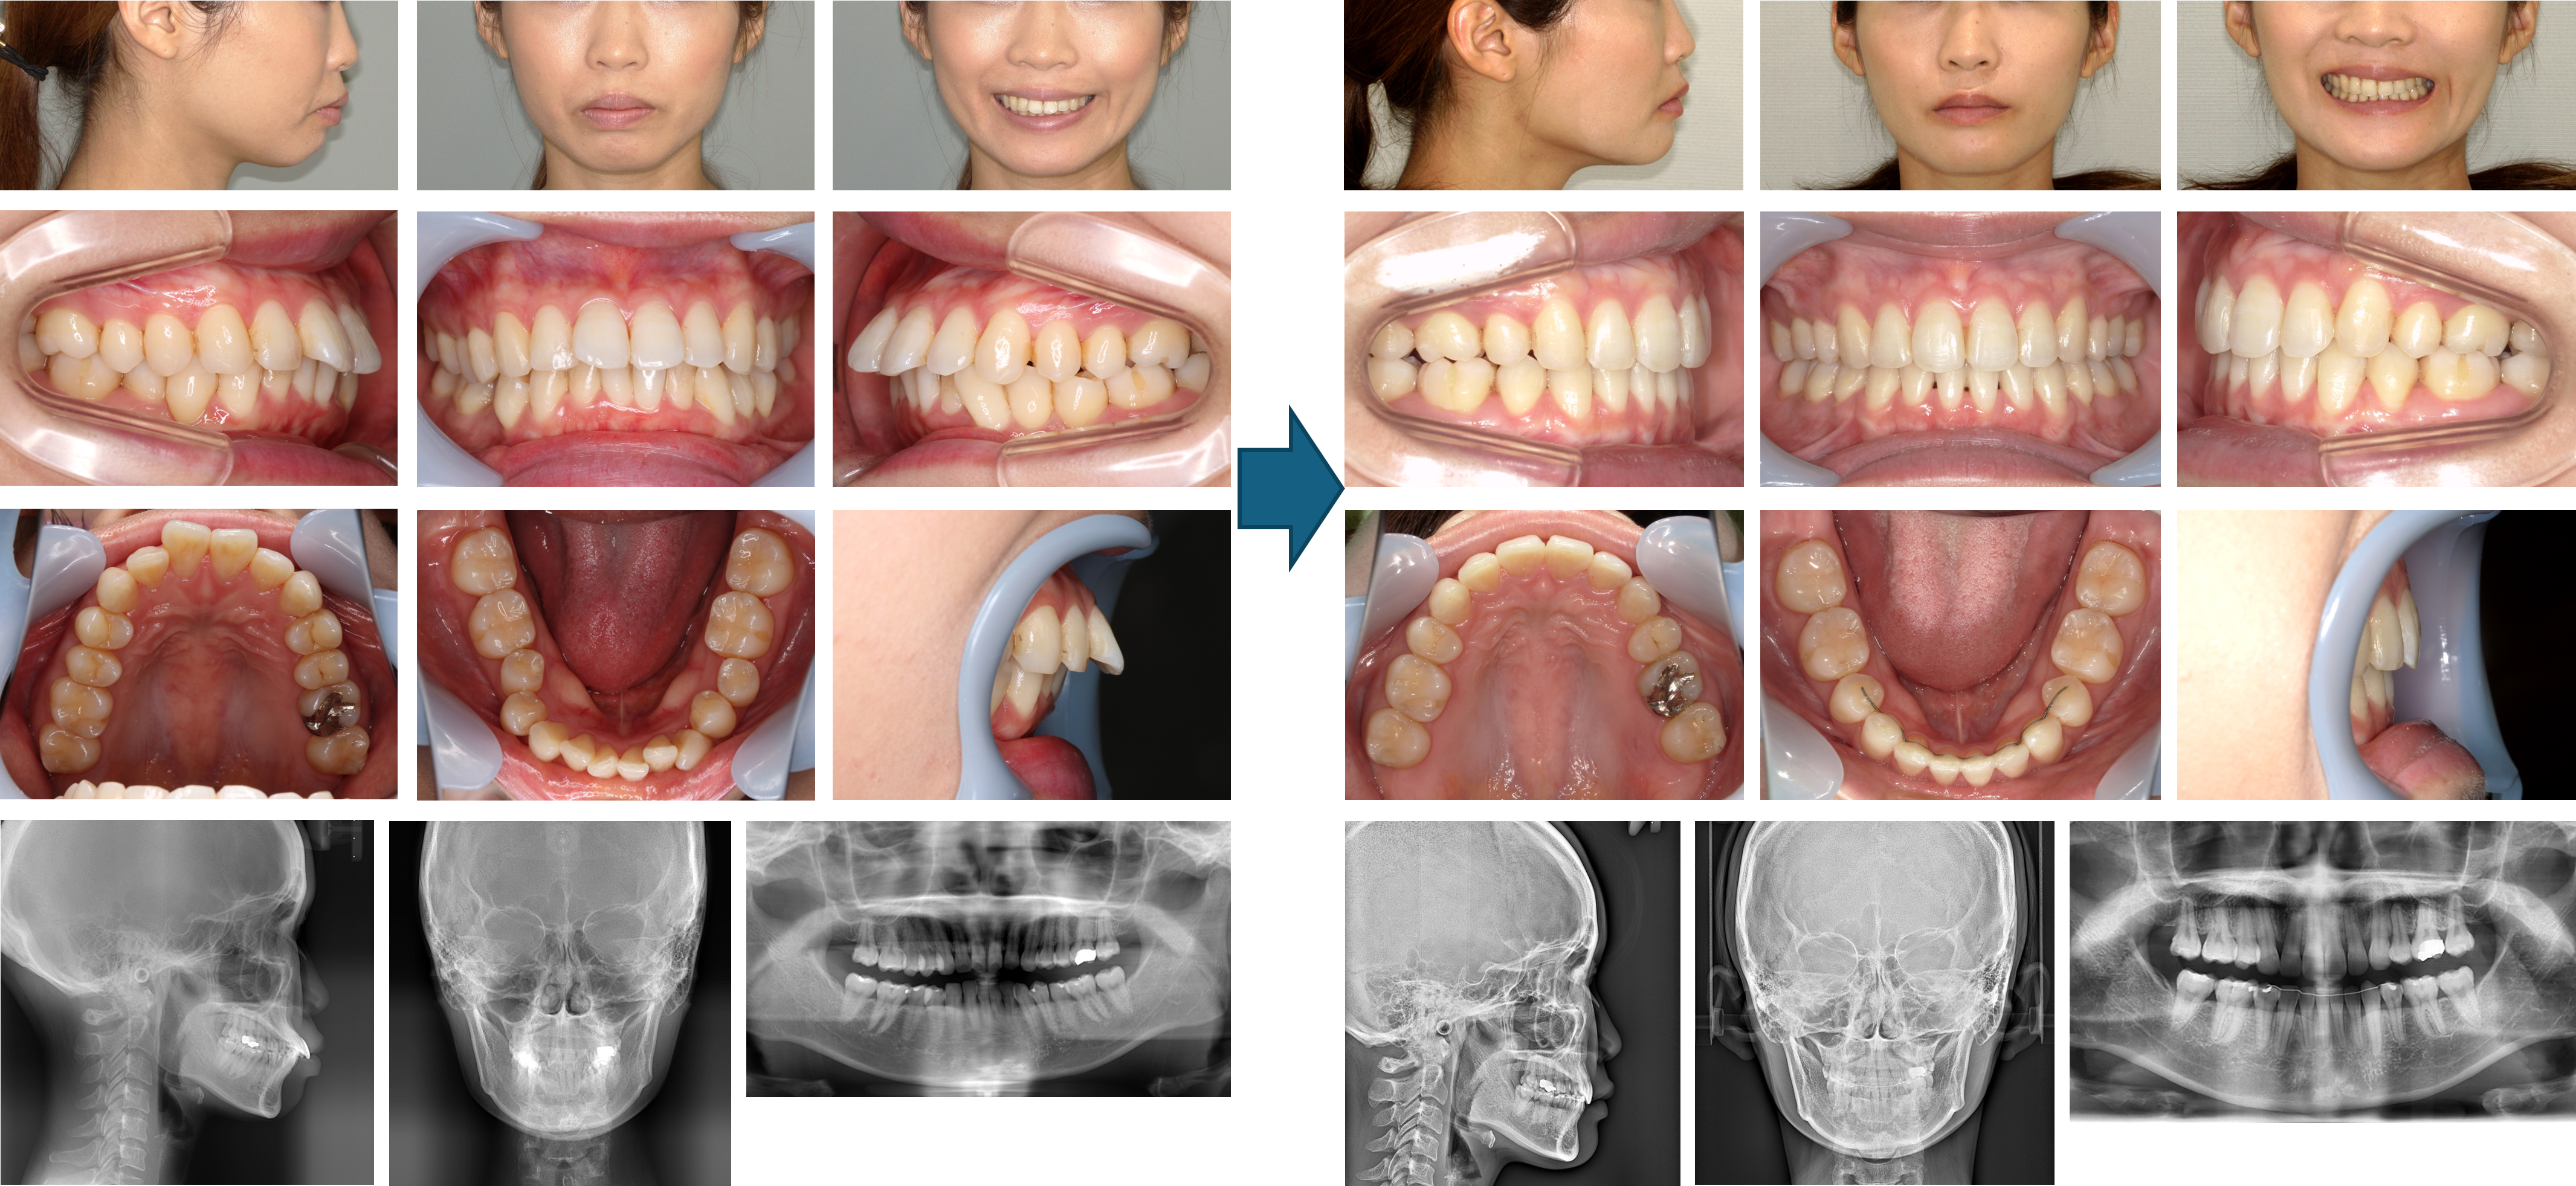

【治療例】初診時年齢:19歳7か月 / 性別:女性 / 主訴:咬み合わせ、たまに口が開かない

症例の概要:この症例は上下の咬み合わせが悪い事とたまに朝に口が開かない事を主訴に来院された。下顎前歯1本(右下2番)が先天性欠如のほか、両側第一小臼歯が鋏状咬合を呈していた。口元の突出感を認めたことから上顎両側第一小臼歯を抜歯した。その結果、開口障害も無くなり、口元の突出感や咬み合わせも改善した。

主訴: 咬み合わせ、たまに口が開かない

診断名: 両側第一小臼歯の鋏状咬合および下顎前歯1歯(右下2番)の先天性欠如を認めた上顎前突症例

使用した主な装置: マルチブラケット装置、歯科矯正用アンカースクリュー、顎間ゴム

抜歯/非抜歯および抜歯部位: 抜歯(上顎両側第一小臼歯)

治療期間:2年0か月

治療回数:30回

リスクの副作用:歯の移動や抜歯による違和感や疼痛、口内炎、歯肉退縮、歯根吸収が生じることがある